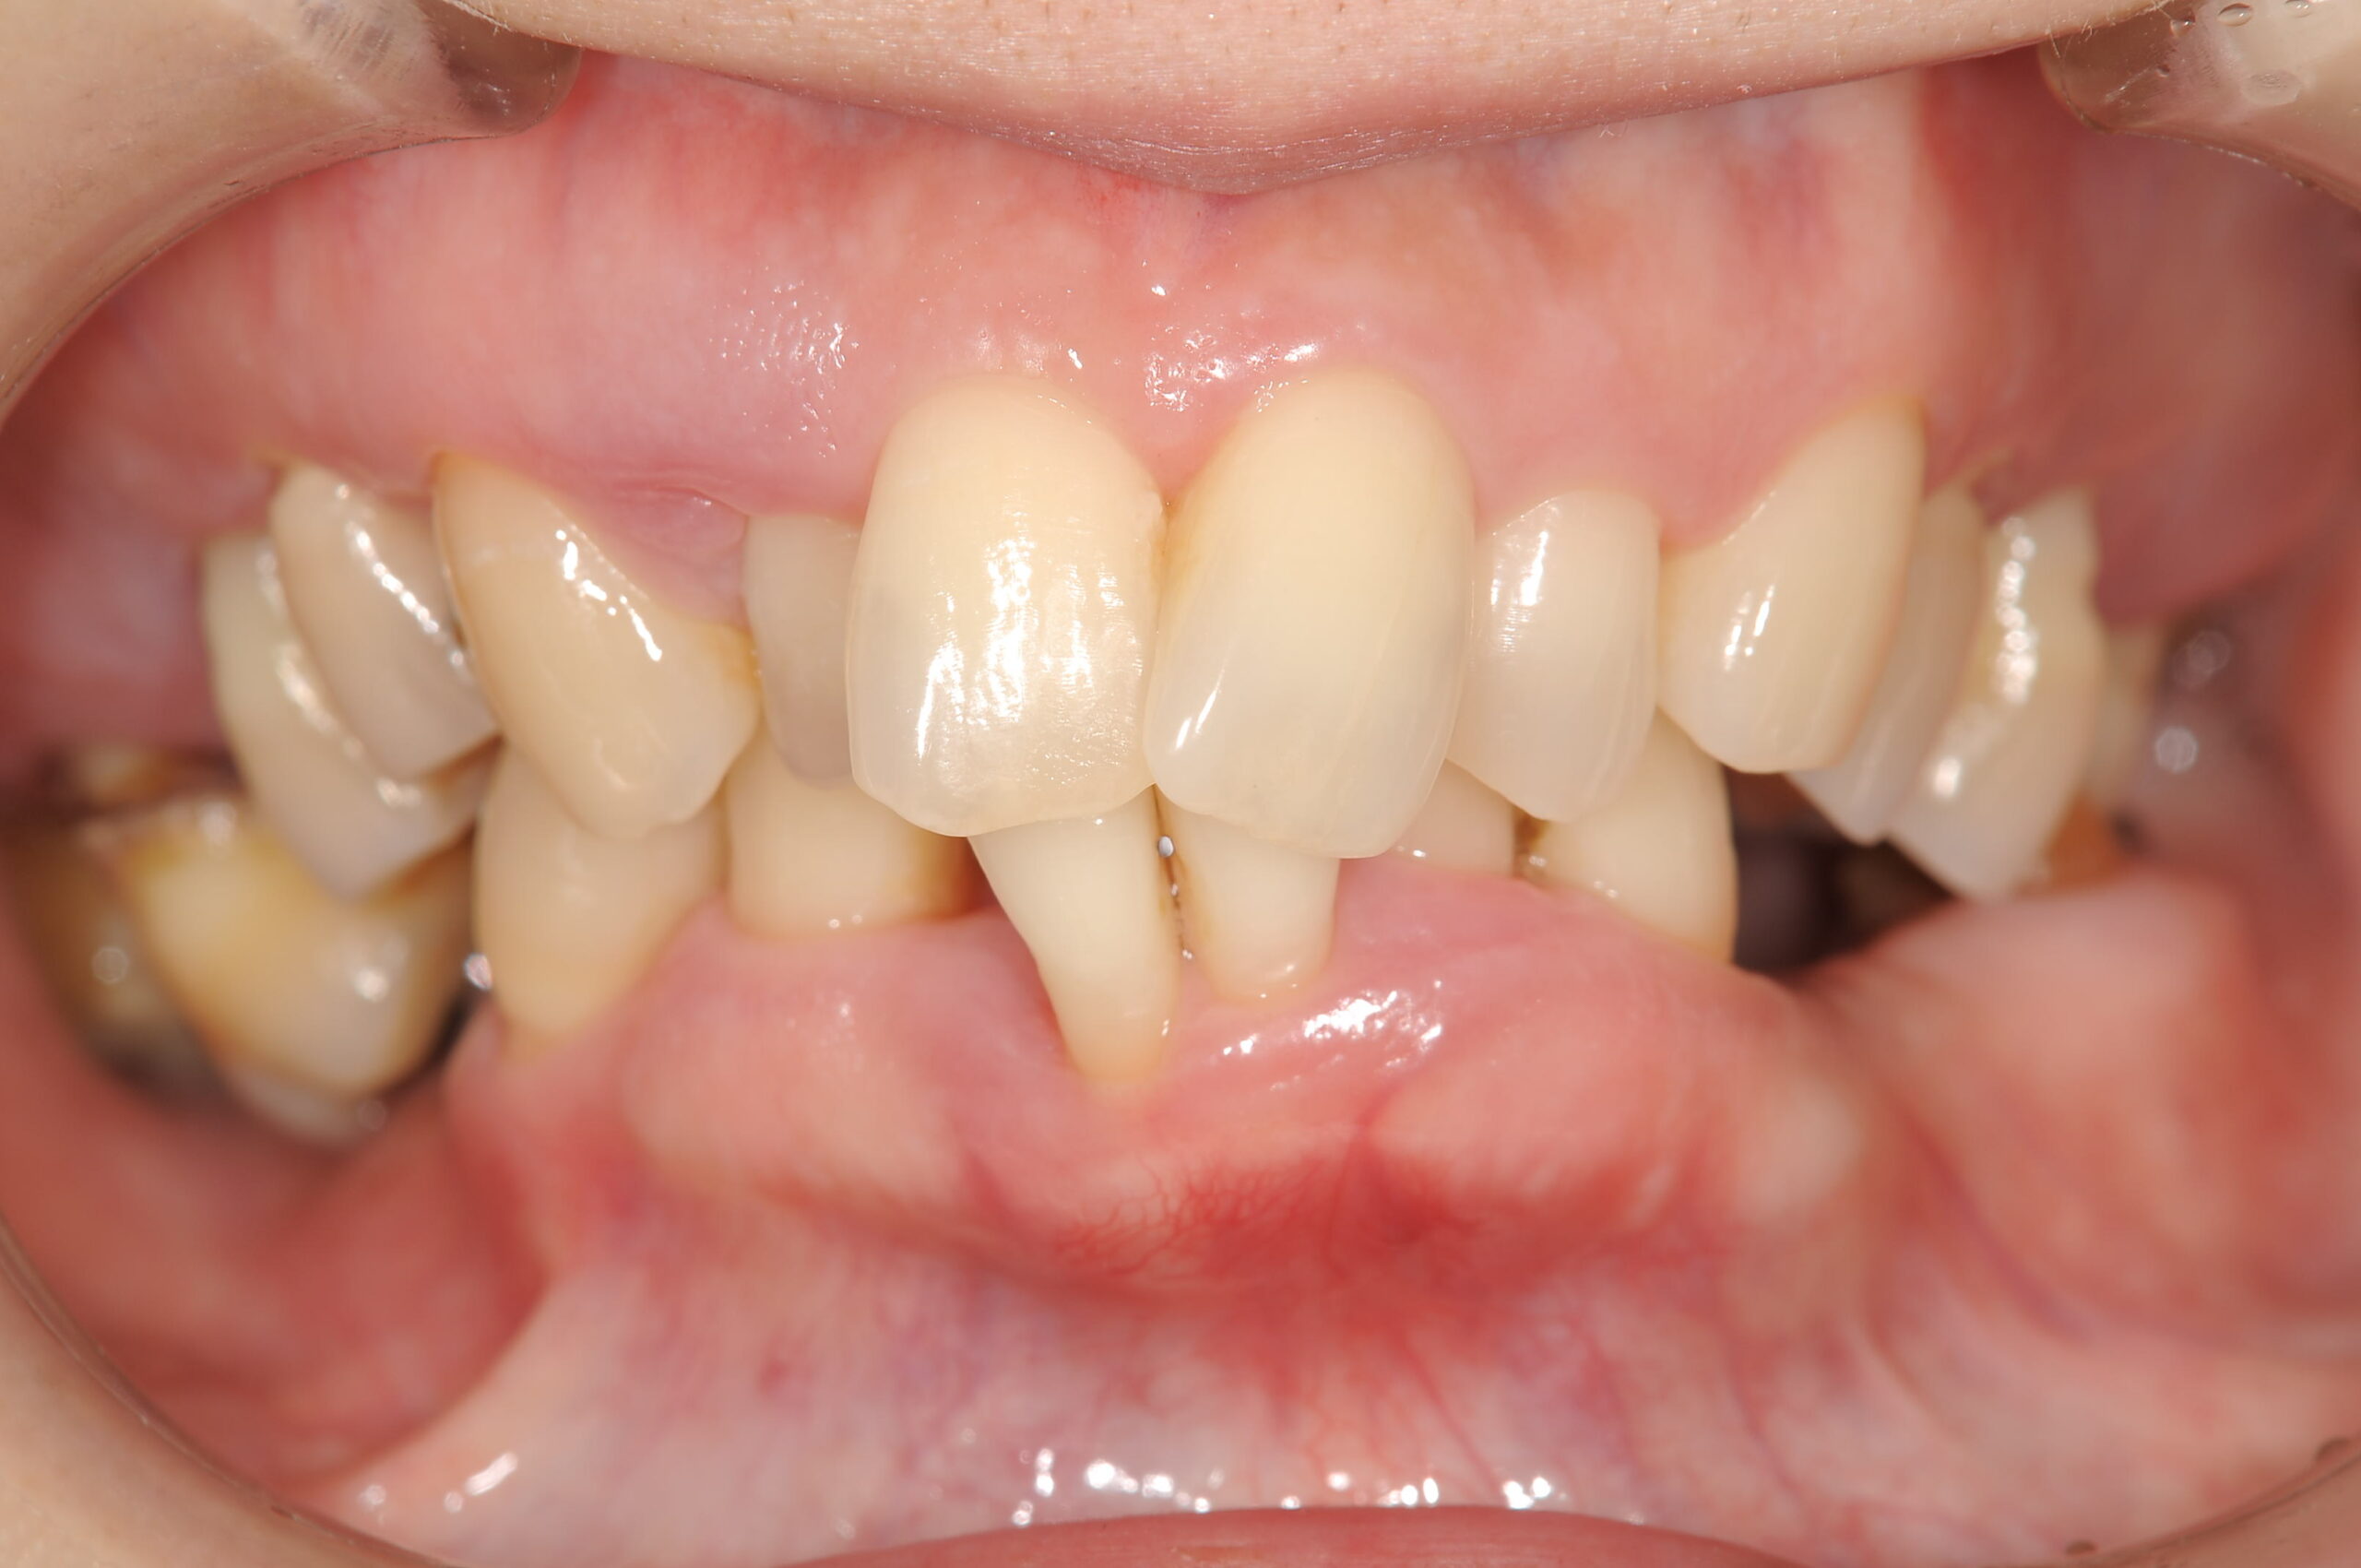

治療前の状態ですが、歯並びの不正とあごの位置もずれが大きく、お口をあけるたびに顎関節にクリック音と痛みがありました。